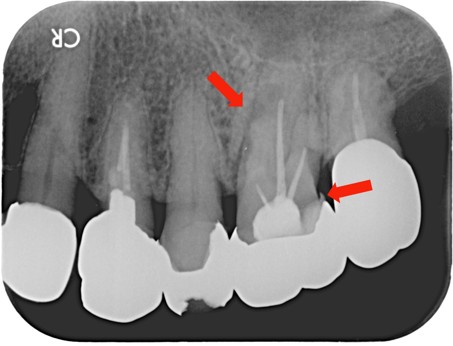

治療後 ![]() |

根の先まで薬を入れることができました。 |